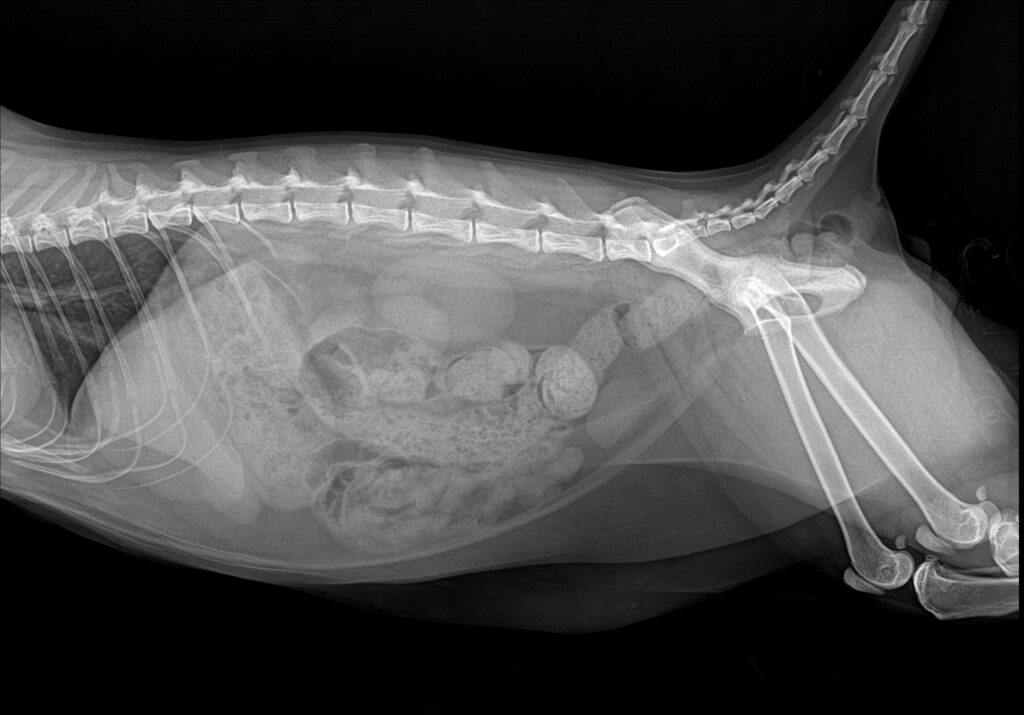

입원 7일차에 톰캣 요도 카테터를 제거한 뒤 자발 배뇨 여부를 집중적으로 모니터링했습니다. 카테터 제거 후에는 복부 방사선 검사와 복부 초음파 검사를 추가로 시행해 방광과 요로 상태를 재평가했습니다.

환자 치료 후 복부방사선 사진/ 출처: 미래 동물의료센터

두 영상 검사 모두 이전에 심하게 팽대되어 있던 방광이 뚜렷하게 줄어든 소견이 확인되었으며 요도 폐색 소견 없이 자발 배뇨가

원활하게 이루어지고 있음을 확인할 수 있었습니다.